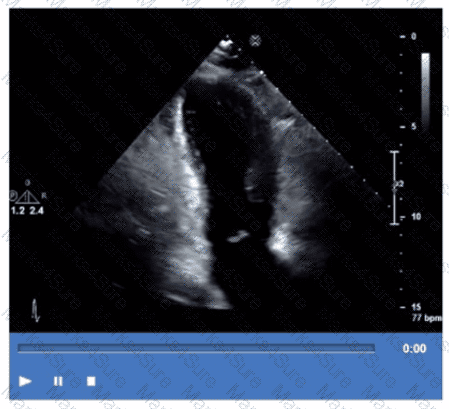

Which coronary artery territory is associated with the wall motion abnormality demonstrated in this video?